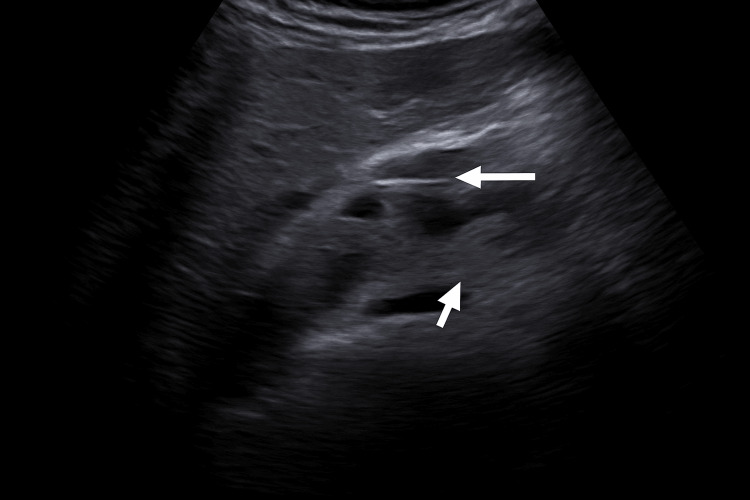

Ultrasound showed intra- and extrahepatic bile duct dilatation (CBD: 15.8 mm), the absence of gallbladder consistent with prior cholecystectomy, and a starry sky pattern. Doppler ultrasound demonstrated the intrapancreatic portion of the CBD and its vascular relations (Figure 1), followed by a confirmatory image with biliary catheter in situ (Figure 2).